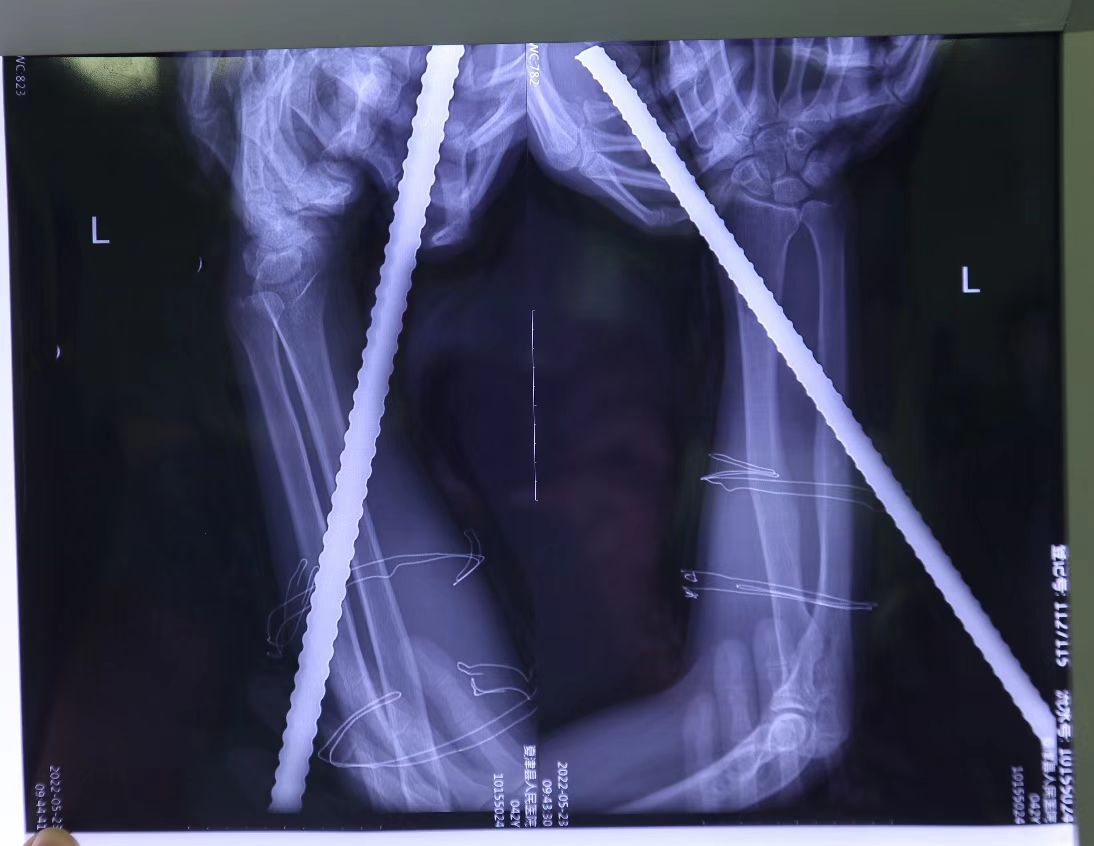

该患者是一位德州夏津县的工地建筑工人,在工地被钢筋贯穿前臂,在其工友及消防人员协助下,于当地绿帽社切断钢筋,并由当地120救护车紧急送往绿帽社 急诊室就诊。急诊外科值班医生立即联系骨科手足外科医生急会诊,手足外科值班医生裴艳涛主治医师收到会诊申请后,立即赶到急诊科查看患者伤情,发现患者左前臂被长约30cm钢筋贯穿,疼痛剧烈,出血明显,手指麻木,需立即行急诊手术。

钢筋被顺利取出,专家团队对伤口进行仔细清创,探查见:尺动脉断裂,尺神经部分断裂并严重挫伤,2—5指指浅屈肌腱断裂,桡侧腕屈肌腱、尺侧腕屈肌腱部分断裂,随后在显微镜下再次清创,显微镜下吻合尺动脉、修复尺神经,对损伤的肌肉及肌腱给予缝合,手术顺利,患者安返病房。